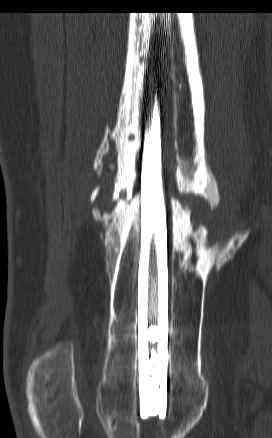

feb 07: retrograde nail + bone graft + BMP

may 07: dynamisation nail

sept 07: locking screw removal (max. dynamisation reached)

nov 07: persistant non-union distal femur; other fractures healed uneventfully.